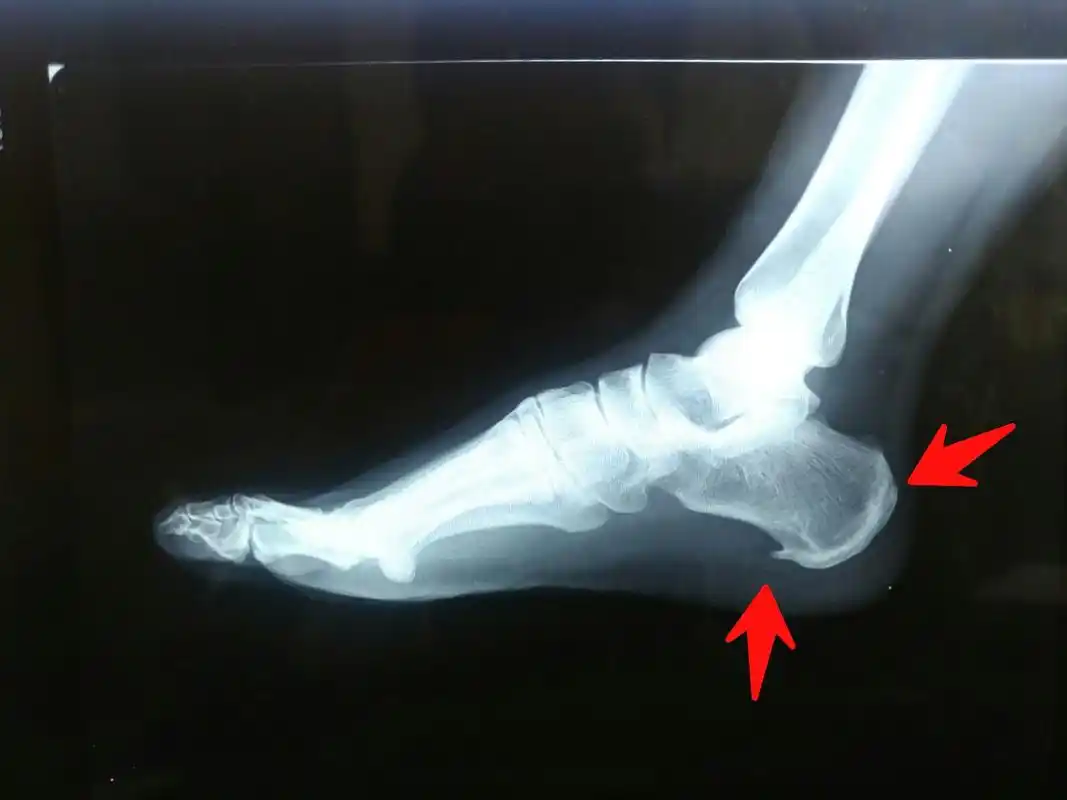

请问如何消除足跟骨刺……先前足跟部有过外伤……伤口复原后,脚没痛

脚后跟骨质增生,请问该怎么治

脚踝扭伤后骨质增生怎么办中医治疗脚踝扭伤后骨质增生

足跟骨质增生 - 知乎